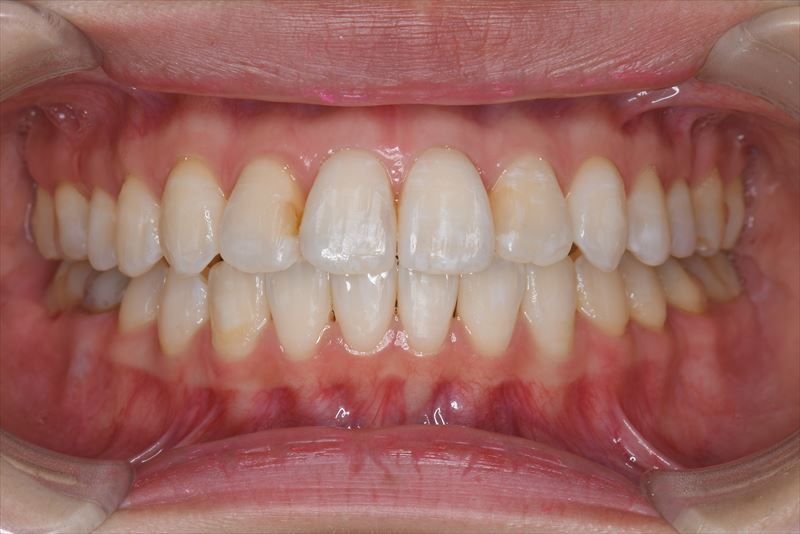

治療後

- 両側2番クロスバイト、叢生、上顎左側6番根尖病巣

- 1年3か月、21回

- 上顎左側6番は失活歯で根尖病巣を認めたため抜歯し、上顎左側8番を代わりに使用することとしました。アンカースクリューを使用することにより、健康な歯を抜歯せず臼歯の遠心移動で叢生の改善できました。治療期間が短かく良好な咬合を獲得できました。